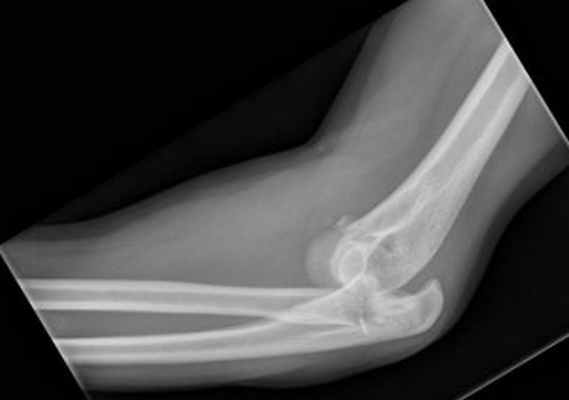

(Слева) На боковой рентгенограмме локтевого сустава визуализируется небольшой отломок перелома кончика локтевого отростка. Края отломка неправильной формы, что отличает это повреждение от несросшегося центра оссификации апофиза.

(Справа) На боковой рентгенограмме у ребенка после падения определяется косой перелом через среднюю точку локтевого отростка с незначительным смещением. Напротив, зона роста локтевого отростка волнистая с выраженным кортикальным слоем по краям. (Слева) На боковой рентгенограмме локтевого сустава после падения на вытянутую руку при согнутом локтевом суставе виден смещенный отломок, оторвавшийся от кончика локтевого отростка. Степень смещения свидетельствует о значительном повреждении трехглавой мышцы.